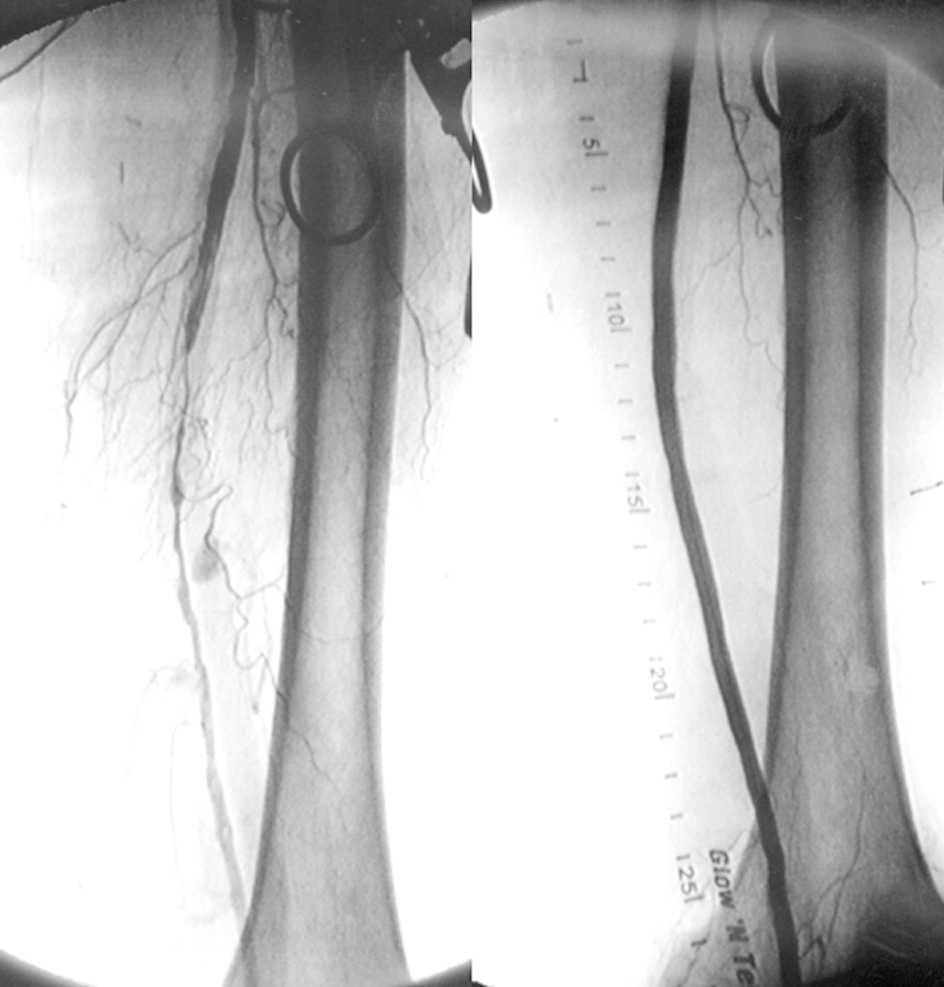

Cuando la isquemia severa de los miembros inferiores no tiene opciones de revascularización con los procedimientos quirúrgicos o endovasculares tradicionales, la arterialización transcatéter de las venas profundas resultó segura y redujo la necesidad de amputaciones. New England Journal of Medicine, 30 de marzo de 2023.

Arterialización transcatéter de las venas de los miembros inferiores para evitar amputaciones